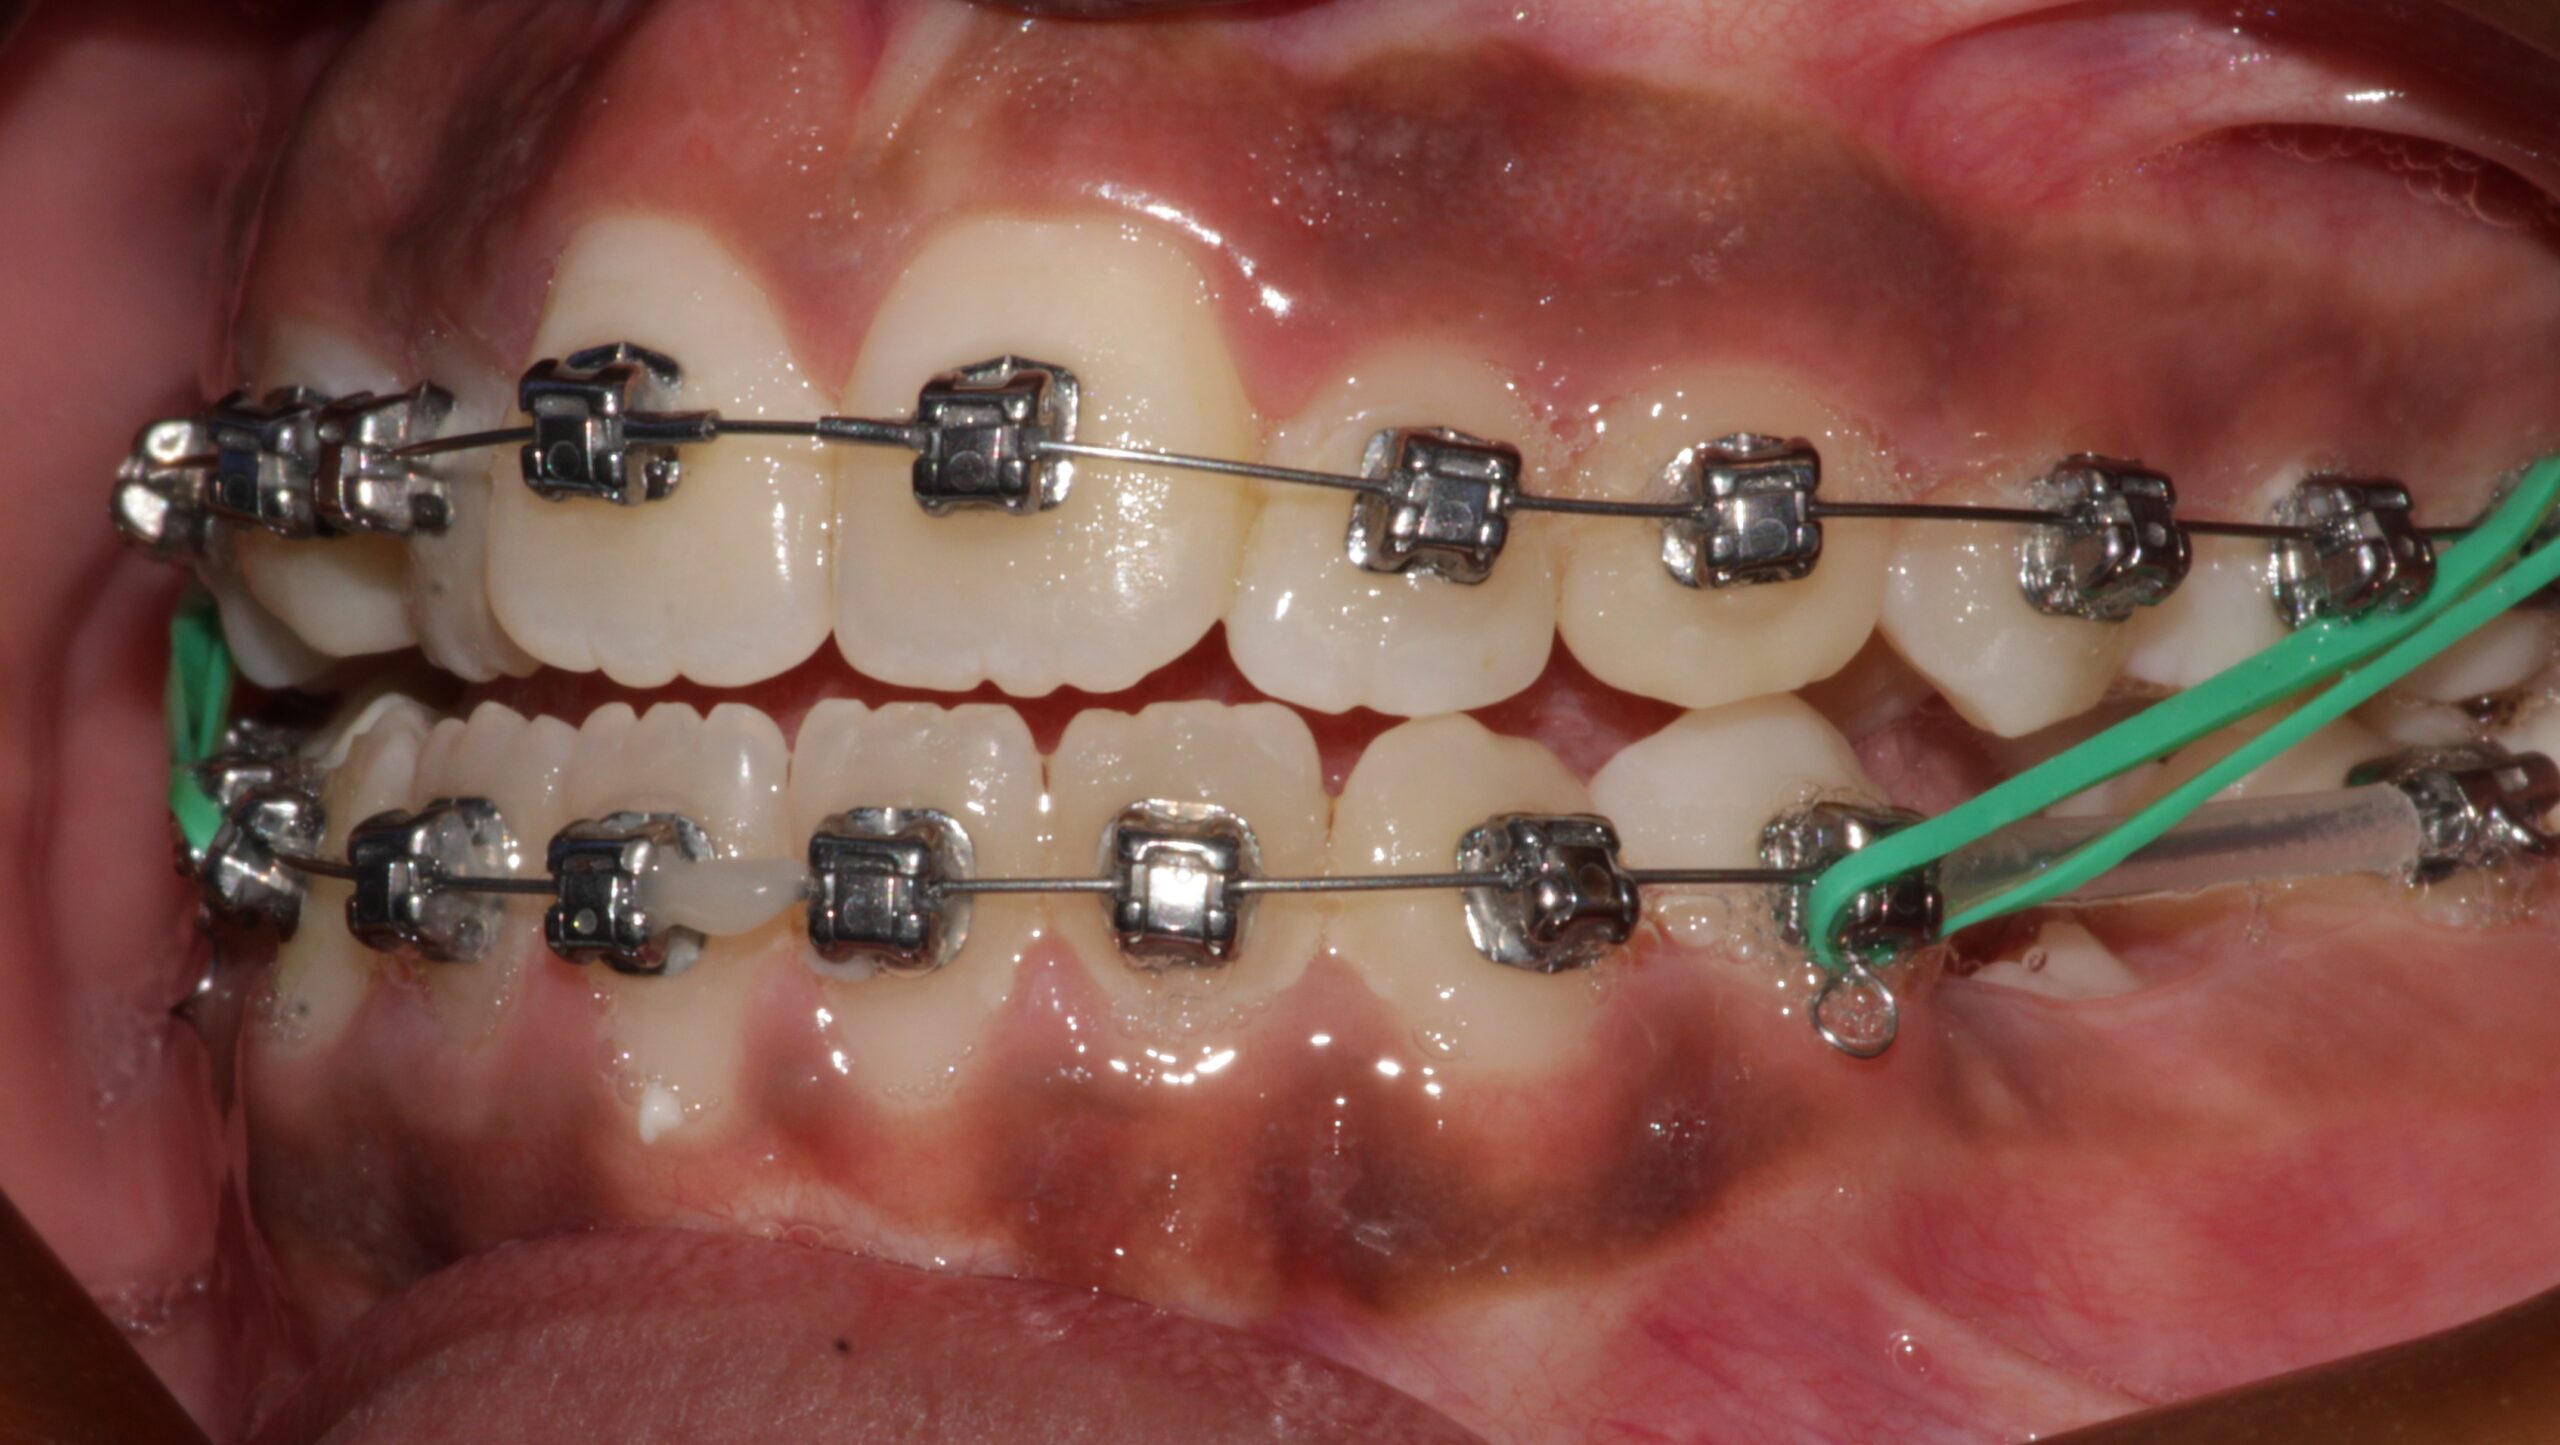

During The Treatment

During The Treatment